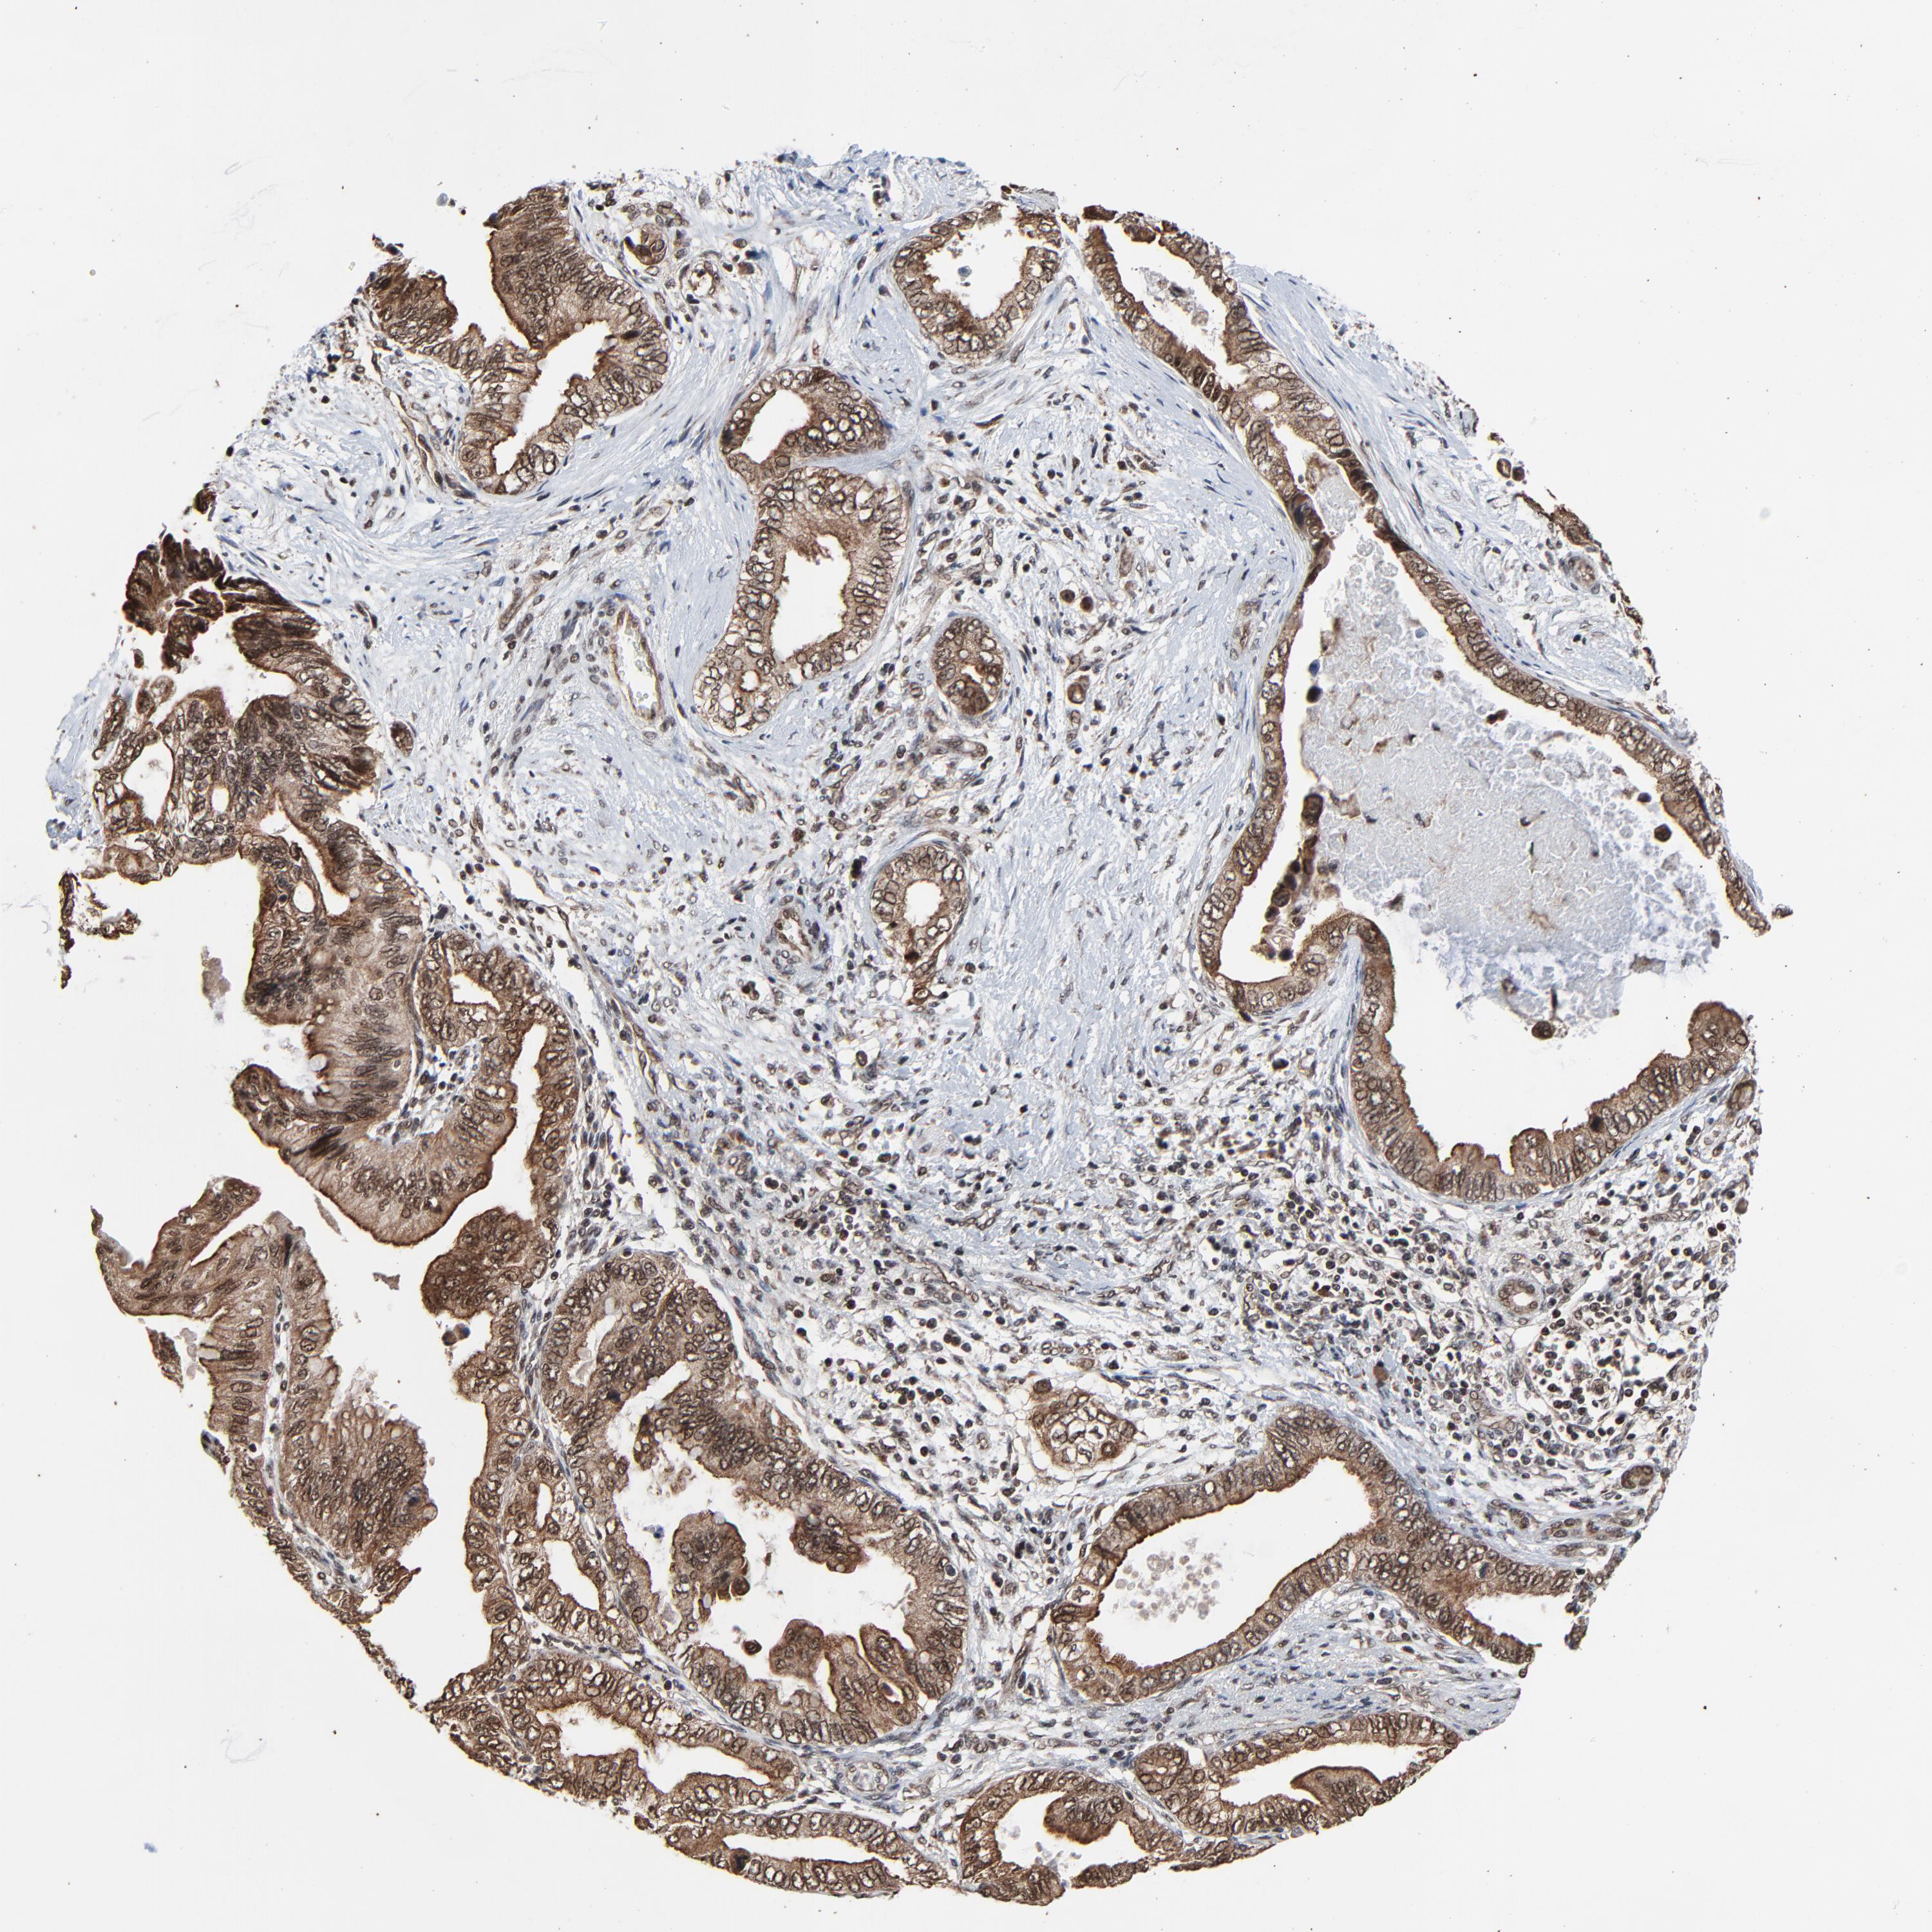

PANCREATIC CANCER - Protein expressioni

A mouse-over function shows sample information and annotation data. Click on an image to view it in a full screen mode. Samples can be filtered based on level of antibody staining by selecting one or several of the following categories: high, medium, low and not detected. The assay and annotation is described here.

Note that samples used for immunohistochemistry by the Human Protein Atlas do not correspond to samples in the TCGA dataset.

Antibody stainingi

Antibody staining in the annotated cell types in the current human tissue is reported as not detected, low, medium, or high, based on conventional immunohistochemistry profiling in selected tissues. This score is based on the combination of the staining intensity and fraction of stained cells.

Each image is clickable and will lead to virtual microscopy that enables deeper exploration of all samples and also displays staining intensity scores, fraction scores and subcellular localization as well as patient and tissue information for each sample.

Antibody HPA003050

Staining

High

Medium

Low

Not detected

Intensity

Strong

Moderate

Weak

Negative

Quantity

>75%

75%-25%

<25%

None

Location

Nuclear

Cytoplasmic/membranous

Cytoplasmic/membranous,nuclear

Adenocarcinoma, NOS